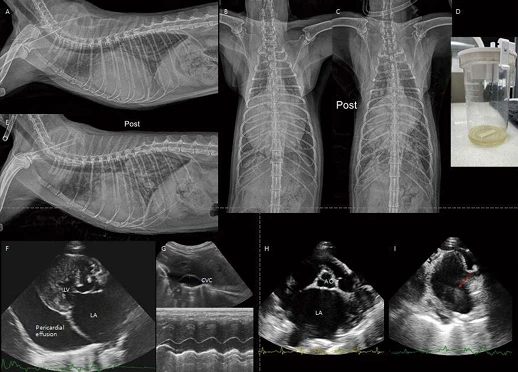

image.png?type=w966

8살 중성화 수컷 5.6kg Persian 고양이가 2일 전부터 급격한 기력 저하, 식욕 감소 증상으로 내원하였습니다. 평소에도 오심 증상이 잦았다고 합니다. 흉부방사선에서 Severe globoid cardiomegaly가 관찰됩니다(A, D). 심음영 내로 장분절 음영이 관찰되기 대문에 바로 PPDH(Peritoneopericardial diaphragmatic hernia) 상태를 고려할 수 있습니다. PPDH 환자에서 심초음파 검사를 하면 일반적으로 심장 옆에 간엽이 잘 관찰되는 편입니다. 그러나 이 환자의 경우 심장 주변으로 지방 및 장 분절만 관찰됩니다. 복부초음파 검사에서 횡격막 스캔 시 간엽 및 담낭이 herniation되어 관찰되는데, 간엽이 작고 울퉁불퉁하며 다수의 myelolipoma (혈관 신호 없는 균질한 고에코성 결절성 음영) 소견이 관찰됩니다(J). CT 검사에서 간엽, 담낭, 소장 분절이 herniation되어 있는 PPDH로 확인됩니다. 초음파 소견과 유사하게, herniation되어 있는 간엽은 심음영이 맞닿아 있지 않고, 작고 울퉁불퉁하며, 다수의 myelolipoma 소견이 관찰됩니다(B, C, E, F, G). PPDH 수술적 교정(H, I) 이후, 환자는 잘 회복하였고, 현재 특별한 임상 증상 없이 모니터링 중입니다.

여기서 잠깐 비교증례!

< PPDH >

3살 중성화 수컷 4.1kg Scottish fold cat이 간헐적인 구토 증상으로 내원하였습니다. 위 환자처럼 흉부방사선 검사에서 Severe globoid cardiomegaly가 관찰됩니다(A, C). 심음영 내로 장분절 음영이 관찰되기 대문에 바로 PPDH를 고려할 수 있습니다. 초음파 검사에서 herniation된 간엽이 작고 울퉁불퉁하며 다수의 myelolipoma 소견이 관찰됩니다(J). CT 검사에서 pericardium 내부로 간엽(quadrate, right medial and left medial lobe), 담낭, 소장 대부분, 대장 일부분, 장간막의 herniation이 관찰됩니다. PPDH로 인한 심장의 압박 및 좌측 두측 변위가 확인됩니다. 초음파 소견과 유사하게, herniation되어 있는 간엽은 작고 울퉁불퉁하며, 다수의 myelolipoma 소견이 관찰됩니다(B, D-I). 위 환자와 다르게 허니아된 간 실질 내 구불구불하게 확장된 측부 혈관(intrahepatic collaterals(E, F, 붉은 화살표))이 관찰됩니다. 이 혈관은 middle hepatic vein을 통하여 후대정맥으로 유입됩니다. 3살의 나이에도 오랫동안 허니아된 간엽의 chronic hypoxia, hepatic venous outflow obstruction 등으로 인해 intrahepatic collaterals까지 생긴 환자로 생각됩니다. 이 환자는 보호자님이 수술을 원치 않고, 보존적 처치만을 원하셨습니다.

PPDH는 간엽 herniation이 기본적으로 많습니다. 오랫동안 허니아된 간엽은 perfusion에 변화가 생기게 됩니다. 즉, 오랫동안 chronic hypoxia, 혈관 또는 림프관의 울혈로 인해 병적 변화가 진행된다고 합니다. 간 조직 검사를 실시해보면, vacuolar to hydropic degeneration, portal fibrosis, myelolipoma 등이 높은 비율로 확인된다고 보고되어 있습니다. 이러한 환자들 중에 시간이 더 지나 malignant changes(fibrosarcoma, cholangiocarcinoma)까지 진행된 증례도 있습니다. PPDH의 수술은 예전에는 임상 증상이 있는 경우, 아직 유착이 적을 것으로 생각되는 젊은 나이에서만 추천되었는데, 최근에는 현재 혈액 검사가 정상 범위라고 하더라도 PPDH로 인해 허니아된 간엽은 chronic perfusion disease 뿐만 아니라, collaterals 혈관들, 종양까지도 진행할 수 있는 위험도가 높아 수술이 좀 더 적극적으로 추천되고 있습니다. 또한 PPDH는 선천적 질환이기 대문에, PPDH 또는 congenital central diaphragmatic hernia 환자에서 nonherniated liver tissue도 ductal plate malformations 상태일 수 있으므로 수술적 교정 시 herniation된 간엽, nonherniation된 간엽 모두 세포조직학적 검사가 추천됩니다.